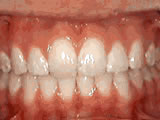

Spacing of teeth

Patient was bothered by the spaces between his teeth. Braces closed the spaces and gave him an ideal bite in 24 months. Special glued-in retainers help keep the spaces closed.